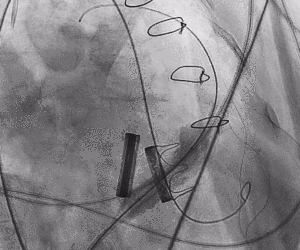

2.进行预扩张。球囊打开时未见明显腰征,预扩张球囊顺利打开梗阻瓣膜。

3.经股静脉入路送入16F E-sheath可扩张导管鞘,随后送入SAPIEN 3球扩瓣1输送系统,由于肺动脉入路朝上走,无需调弯,顺利跨瓣,将SAPIEN 3球扩瓣送入预定位置。精准定位后,以160次/分快速起搏,并保证1:1完全夺获,缓慢释放瓣膜。术后超声检查结果显示即刻跨瓣压差从术前9mmHg降至3mmHg,顺利完成瓣膜释放,回撤导管、导丝。